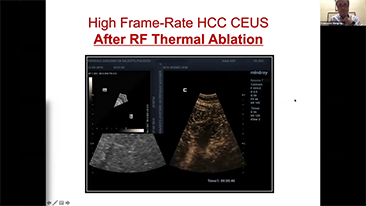

Mindray Resona Genel G?rĂŒntĂŒleme ??zĂŒmleri, kapsaml? alt b?lĂŒm uygulama problar? ve verimli klinik uygulama ara?lar? arac?l???yla, klinisyenlerin daha do?ru ve verimli tan? ve tedavi sonu?lar? elde etmesine yard?mc? olur.